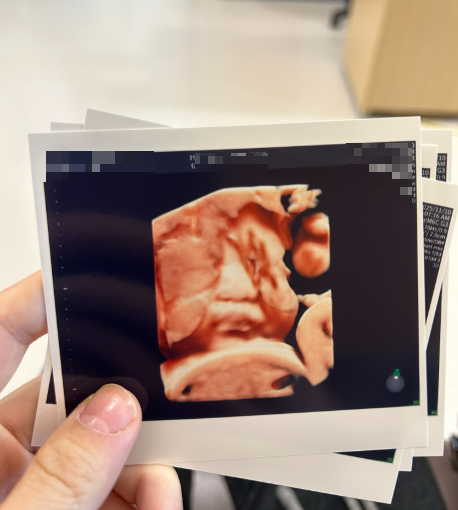

쌍둥이 임신 33주 마지막 초음파 사진

3. 쌍둥이 임신 33주차 태아 체중

선둥이: 1702g

후둥이: 2202g

2주전보다 후둥이가 많이 커서 살짝 놀랬고, 아직 성장 차이는 괜찮은 정도였습니다!